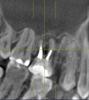

belbucha Опубликовано 29 января, 2011 Поделиться Опубликовано 29 января, 2011 Доброго времени суток всем.Несколько дней назад начали беспокоить очень сильные боли в области гайморовой пазухи и зубов с правой стороны. Сделал рентген снимок для ЛОРа, направили к нему с диагнозом гайморит.В больнице сделали прокол, увидели много гноя, сказали сделать КТ, дабы исключить вариант заболевания от зубов (одонтогенного генеза), т.к. не было у меня ни соплей, ни еще каких-либо симптомов, кроме боли.Сделали КТ, и выдали вот такое заключение: "В правой верхнечелюстной пазухе визуализируется мягкотканное содержание с пузырьками воздуха в своем составе, занимающее 2/3 всей полости, одонтогенного генеза (16 зуб радикулярная киста медиального щечного корня проросла в правую в/ч пазуху, разрушив костное дно). В левой в/ч пазухе определяется утолщение слизистой нижней стенки до 7-9мм одонтогенного генеза, причиной была радикулярная киста медиального щечного корня 26 зуба. Передние и средние ячейки решетчатого лабиринта справа, заполнены мягкотканным содержимым, слизистая гипертрофирована. Основной (клиновидный) синус - незначительное утолщение нижней стенки. Заключение: КТ картина соответствует правостороннему гнойному одонтогенному гаймориту. Этмоидиту. Радикулярная киста 16,15,26 зубов." На руках у меня только заключение и диск с КТ, снимков нет. У меня нет медицинского образования, но насколько я смог увидеть хоть что-то, выкладываю скриншоты КТ.При необходимости, могу выложить на какой-нибудь обменник весь диск, ISO-образ его. Скажите люди добрые, что меня ждет? что можно предпринять в таком случае? Очень не хочется остаться без жевательных зубов в 25 лет. Период сейчас крайне сложный, супруга на 9-ом месяце, ей нужна моя помощь и поддержка, некогда мне по болницам лежать.Заранее всем спасибо. Ссылка на комментарий

Scrabble Опубликовано 29 января, 2011 Поделиться Опубликовано 29 января, 2011 С 16 неоднозначно-может быть, и удалить придётся, 26-27 перелечите у эндодонтиста. 15 корень удаляется, похоже. Ссылка на комментарий

Bier Опубликовано 29 января, 2011 Поделиться Опубликовано 29 января, 2011 надо еще прицельные снимки сделать. Если возможно перелечить - перелечивайте, если нет - удаляйте. Потом имплантаты поставите. Ссылка на комментарий